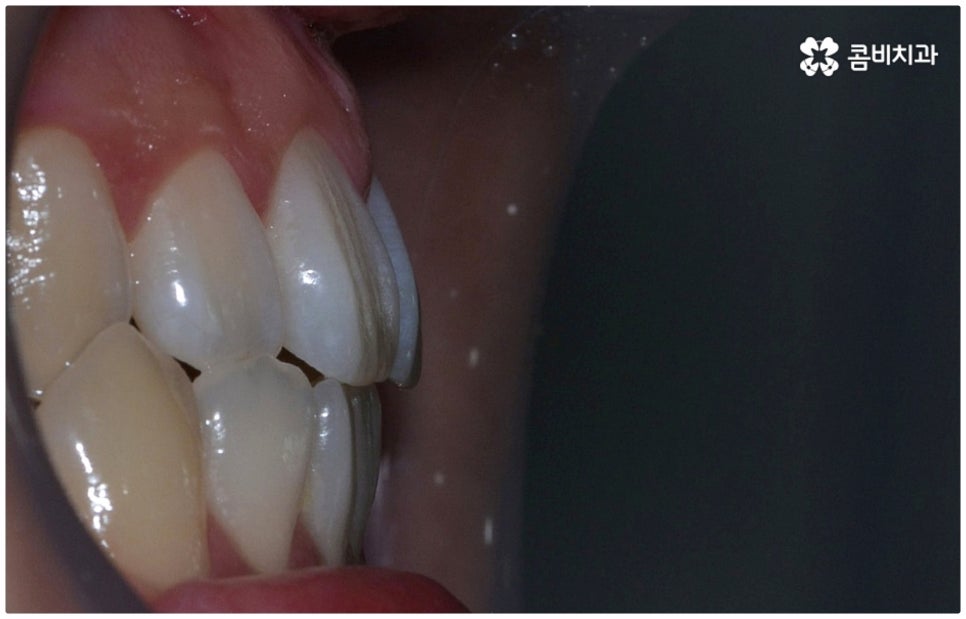

부정교합 3급 이란 입을 다물었을 때 아래 어금니가 윗 어금니보다 전방에 위치한 경우를 가리키는 것으로 그 중 절단교합은 이 상태에서 위아래 앞니 끝과 끝이 맞닿는 교합을 의미하는 거예요. 이에 비해 정상적인 교합은 어금니는 똑바로 맞물리고 윗 앞니는 아랫 앞니를 살짝 덮는 정도로 겹쳐지면서 자연스럽게 조금 앞으로 나와 있는 상태를 말하고 있습니다.

이때 심하지 않은 절단교합의 경우 환자분들의 입장에서는 하악이 상악보다 상대적으로 튀어나와 주걱턱처럼 보이는 정도가 그렇게까지 크지는 않다 느끼실 수 있는데요. 특히 또 다른 부정교합 3급 케이스 중 하나인 반대교합 (아래 앞니가 윗 앞니보다 더 앞으로 나가 거꾸로 물리는 경우) 과 비교해 보면 더욱 심각하게 생각되지 않을 수 있어요.

그러나 현재는 이를 바로잡지 않으면 위아래 앞니 사이의 공간이 없기 때문에 어금니가 음식물을 잘게 자르고 부수는 역할을 할 때 생기는 교합력이 앞니에 그대로 전해져서 큰 부담을 주게 되고, 앞니 끝이 부딪히면서 마모가 되거나 치아 수명을 짧아지게 만드는 원인으로 작용하게 될 수 있습니다. 저작 기능을 할 때마다, 즉 식사를 하면서 음식물을 씹을 때마다 치아와 잇몸에 무리한 힘을 가하여 약해지게 만들고 치근까지 좋지 않은 영향을 받게 되는 상황이 발생하므로 교정 치료를 통해 하루 빨리 개선해 주시는 게 좋을 거예요. 특히 절단교합 케이스에서 과도한 교합력이 걸리는 앞니는 심미적으로나 기능적으로나 굉장히 중요한 치아이기 때문에 더욱 주의하실 필요가 있어요.

물론 교정 치료에 적기가 정해져 있는 것은 아니기 때문에 성인 이후 중장년 환자분들이라도 교정 치료가 불가능하지는 않으며 상황에 따라 비수술적인 방법으로도 얼마든지 불편함을 줄일 수 있는 경우가 있으니 정확하게 진단한 후 각자에게 맞는 교정 계획을 세워 무리하지 않게 치료를 진행하시길 바라고 있어요. 특히 턱관절과 관련된 부분을 개선하기 위해서는 양악 수술 밖에 방법이 없는 것이 아닌가 생각하셨던 분들이라면 먼저 치과에 내원하셔서 검진과 상담부터 진행해 보시면 마음의 부담을 덜 수 있어 좋을 거예요. 부정교합 3급 치열 (절단교합과 일부 반대교합이 병행되어 있음) 을 가지고 있는 성인분도 교정 치료를 통해 훨씬 자연스럽게 개선이 가능할 수 있으며, 관련 기술 개발 및 미니스크류 등 여러 장치의 발전을 통해 예전에는 적용이 어려웠던 케이스들도 이제는 교정 치료의 도움을 받을 수 있습니다.